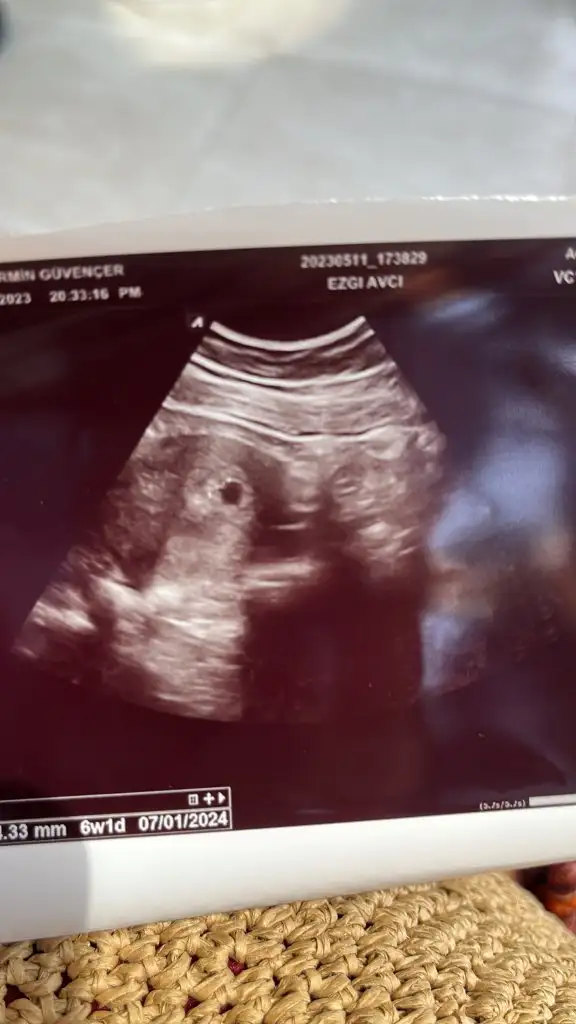

Bebegin konumu Tam net belli degil kuzum göremiyorum cuma günü tekrar atSelam canımcımlar benim bugün aşırı tansiyonum düştü ve miğdem bulandı doktora gittim istersen serum takalım dedi ben gerek yok dedim . Suyu az tüketirsek tansiyon düşermiş haberimiz olsungünde en az 10 bardak su iç dedi birde kesemiz doluymuş şükür ama perşembe günü 4+3 demişti bugün 6+1 dedi anlamadım bende sizinde öyle olmuşmuydu. Çok az kalp atışı aldı net duyamadım dedi cuma günü gel karından kalp atışını duymazsam vajinal bakarım dedi. Siz kaç haftalıkta duydunuz kalp atşını birde melegim can karnımdan baktı ama daha erken mi cinsiyet için

Vajinal ise erkek gibi canımYorumlayabilir misin acaba vajinal ultrason 6+5